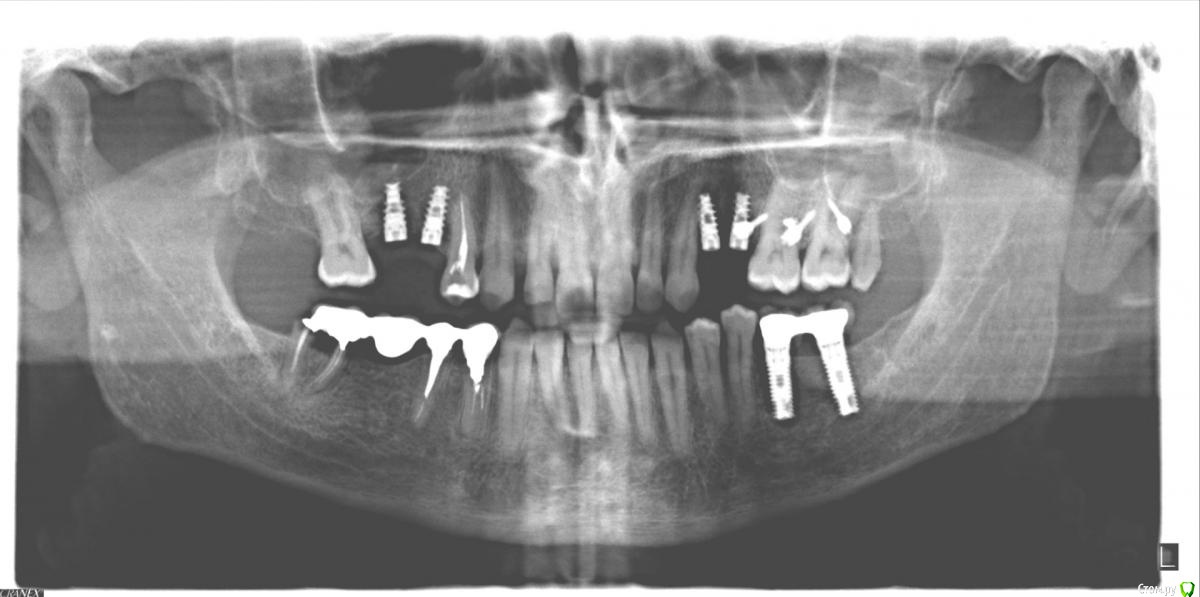

LK9722 Опубликовано 20 февраля, 2015 Поделиться Опубликовано 20 февраля, 2015 Прошу совета. Незаметно на верхних правых (по рентгену) 6 и 7 появился кариес, то есть я видел только маленькую точку на боковом торце 6-ки и тщательно чистил их, и эта точка в таком состоянии много-много лет, с 2005 или даже раньше. И вдруг безо всякой нагрузки откололся кусок верхней 7-ки, откололся настолько легко что похоже было что прогнил зуб капитально.Причем на всю толщину зуба, то есть как бы 1\5 зуба но вертикально, по самый корень. При этом до самого откалывания боли не было, и кариес был нетипичным когда сначала дырка потом болит потом только начинает разрушаться, здесь этого не было. После того как откололся кусочек я сделал орто (там видно это), но особой боли при накусывании не было и только через несколько дней после снимка вдруг появились классические признаки (похоже что дело дошло до пульпы и стало больно накусывать зубом). После этого начали его лечить и почему-то один из каналов резко отличался от двух других, т.е. сразу стало понятно что он проблемный, два канала уже на второй визит были сухие и готовые к пломбированию, а этот канал парил мозг еще около 5-6 недель, продолжал кровить и вроде бы запах показывал что там не все ОК. И чувствительность показывала что в отличие от двух других, этот канал проблемный. Вопрос, видно ли по снимку что кроме отколовшегося кусочка зуба там еще и проблемный корень ? Вообще что можете сказать про эту правую 7-ку ? Откуда пошел кариес, сверху или от корня ? Прилагаю снимки с 2011 года по декабрь 2014. Еще есть такие вопросы. 1. Зуб верхняя 6-ка имеет ли рентген-признаки кариеса ? Сейчас скоро будем ставить коронку на 7-ку и важно понять, нужно ли с заднего торца 6ки пролечить темные точки если они там найдутся ? Я вижу что на переднем торце такая точка есть много лет. Хочется решить вопрос с 6-кой прежде чем новая коронка на 7 зубе закроет доступ к торцу 6-ки. 2. Зуб 8-ка (маленький и ненужный) лучше удалить нафиг ? 3. Есть ли признаки кариеса на левой верхней 6-ке ? 4. Что скажете про импланты (про все 6 штук), и что лучше ставить на нижние импланты - сваренные вместе коронки или отдельные ? 5. Верхняя правая 4-ка с пролеченными каналами, с 2011 года при постукивании и накусывании не то чтобы болит, но немного не так себя ведет чем все остальные живые или леченые зубы. Можно сказать почти не ощутимая боль есть. Доктору я говорил что после лечения каналов чуть больно было нажимать рядом с носом (где корень заканчивается верхнего этого зуба). Прилагаю отдельный снимок этого зуба (от 2011 года). Что можно сказать про него в динамике, от 2011 до 2014 года ? Можно ли его в таком состоянии накрывать вкладкой и коронкой ? Сейчас он с пломбой с тех пор, уже более 3х лет. 6. На первом снимке виден нижний мост, который прослужил с 2004 по 2009 а потом стал болтаться на 6 зубе, проходил еще до 2013 года и наконец слетел. Выяснилось что от опорной нижней 6ки ничего не осталось, его обпилили и оставили половину. Керамика на нем начала отлетать лет через 5 почему-то на мало нагруженном зубе, на нижней 4-ке (керамика Noritake).А на болтающейся 6-ке керамика была в порядке до последнего дня. Странно... Что про этот мост скажете, нормально он пожил или маловато ? Ссылка на комментарий

LK9722 Опубликовано 20 февраля, 2015 Автор Поделиться Опубликовано 20 февраля, 2015 второй снимок, после лечения верхней 4-ки и установки имплантов сверху. Не понимаю, как прикрепить следующие фото. У меня их 5 штук ! Ссылка на комментарий